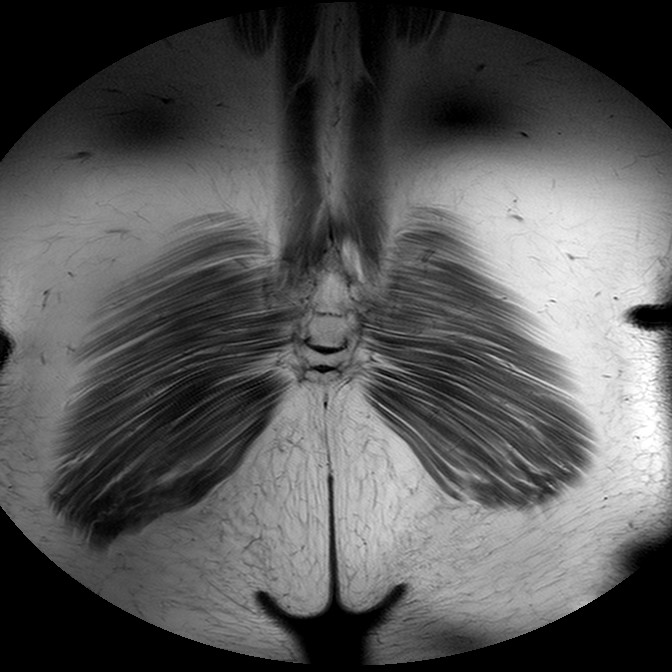

Esami: RMN BACINO

T1w TSE

Evidenti e simmetriche alterazioni osteofitosiche in regione coxo femorale con riduzione delle rime articolari. Degenerazione completa del cercine glenoideo. Non attuali segni di versamento articolare. Non segni di edema osseo che escludono attuale algodistrofia od osteonecrosi. Lieve e simmetrica riduzione del trofismo della muscolatura glutea.